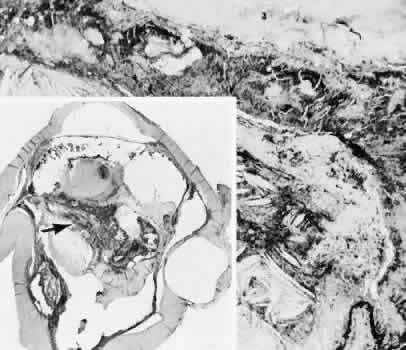

that results in reestablishment of functional ocular anatomy.1–3 The goal of therapeutic intervention in the setting of ocular trauma is to promote the repair process and to allow it to proceed as rapidly as possible and heal as completely as possible without compromising ocular function.4 CELLULAR AND EXTRACELLULAR COMPONENTS The four basic cell types found in wound healing are fibroblasts, vascular endothelial cells, inflammatory cells, and epithelial cells. Specialized cell types that participate in ocular wound healing include corneal endothelial cells, retinal pigment epithelial cells, and Müller cells of the retina. Specific cell populations enter an area of injury under the influence of complex biochemical and biophysical processes involving proteins of the extracellular matrix and the coagulation system. Intracellular proteins, such as tubulin and actin, andmyosin filaments function in cell locomotion. Extracellular matrix proteins, such as fibronectin, laminin, and type IV collagen, orient and regulate cell migration and adhesion.5 Coagulation proteins, such as von Willebrand's factor and plasminogen, alsofunction in regulating the cellular events of healing. Vascular endothelial cells are stimulated to leave their resting state and digest basement membrane, proliferate, migrate, and eventually differentiate under the direction of multiple angiogenic growth factors.6 A wound usually is filled first by a fibrin coagulum. Neutrophils, lymphocytes, and histiocytes (macrophages) enter the wound through fibrin scaffolding to clear necrotic debris and confine toxic or foreign substances. Granulation tissue often is the first type of reparative tissue in wound healing (Fig. 1). Although its composition varies somewhat, small-caliber vascular channels in a delicate collagenous stroma infiltrated by acute and chronic inflammatory cells generally characterize it. This amorphous tissue serves as a template for more definitive repair. Metaplasia is the transformation of a cell from one adult cell phenotype to a second cell phenotype. In advanced wound healing, fibroblasts acquire intracytoplasmic characteristics of smooth muscle cells (myofibroblasts).7 The myofibroblasts are able to contract and bring wound edges together. Vascular endothelial cells proliferate and migrate into the wound from preexisting adjacent vessels. The new “vessel” migrates initially as a solid bulb of endothelial cells. This solid cord of cells will canalize and differentiate into mature arterioles, venules, and capillaries. Fibroblasts grow into the wound in a radial manner but will eventually reorient and secrete collagen along lines of established tissue tension. Epithelial cells are found covering surfaces of tissue. Two distinct types of epithelial cells cover the ocular surface: corneal epithelial cells and conjunctival epithelial cells. Cell replacement is accomplished by stem cells located at the limbus for the corneal epithelium8,9 and at the mucocutaneous junction and possibly throughout the conjunctiva for the conjunctival epithelium.10 Migration and proliferation of surrounding healthy epithelial cells heal surface discontinuity. Apoptosis is a biochemical process leading to programmed cell death. Cell death in apoptosis results from intracellular messages. In necrosis, cell death results from toxic external factors (e.g., hyperosmolality). Apoptosis allows for elimination of entire populations of cells without tissue damage or an inflammatory response.11 Elimination of certain cells is advantageous in embryology (e.g., when scaffolding structures are no longer necessary as with the primary vitreous). In certain neoplastic conditions, however, defects in apoptosis may lead to disadvantageous accumulation of cells. Apoptosis also seems to be highly influential in all types of inflammation, including wound healing. In wound healing, apoptosis may function to control the type and degree of tissue response.12 In the anterior cornea, keratocytes have been observed to undergo apoptosis in response to wounding of the cornea.13,14 Abnormalities of apoptosis may be responsible for such conditions as keloid formation in the skin15 and keratoconus in the cornea.16 Wound healing of highly specialized tissues of the eye has several unique features. CORNEAL HEALING The healing of the cornea is unique relative to other soft tissues, because it lacks blood vessels and because it is lined anteriorly and posteriorly by layers of epithelial-like cells. Epithelial cells of the corneacan produce essential wound healing factors normally produced by platelets.17 Architectural repair is accomplished at the level of the corneal stroma. Abrasions are injuries generally involving only the superficial layer (epithelium) of the cornea (Fig. 2). Abrasions are commonly caused by mechanical injuries or anoxia resulting from contact lens overwear. Some or all of the layers of the surface epithelium are lost, but Bowman's membrane remains intact. After a delay of approximately 1 hour, uninjured epithelial cells at the margin of the wound loosen their intercellular and basal attachments and migrate en masse toward the injured area.18 The shape of the wound margin and the biochemical characteristics of the exposed tissue influence the direction and extent of the migration.19 If the entire corneal epithelium is abraded, migrating epithelial cells derived from the limbal stem cells are able to cover the defect completely within 48 to 72 hours. The epithelium will be much thinner than normal until mitotic division reestablishes normal thickness. Re-formation of epithelial basement membrane may not be detectable for as long as 6 weeks after injury.20 Clinically, the healed wound is transparent. Small defects of Bowman's membrane (Fig. 3) do not heal by fibrous proliferation of the stroma. The defect is filled by proliferating epithelial cells (epithelial facet formation) that reestablish the surface continuity of the cornea. The facet may be seen clinically as a focal, well-demarcated, superficial corneal opacity. A corneal foreign body causes this lesion most often. Penetrating corneal injuries involving at least one third of the stroma (Fig. 4) are covered initially by proliferating surface epithelium that may extend for a considerable distance into the stroma. The extent of corneal epithelial migration is controlled at least in part by contact inhibition of migration once contact with healthy corneal endothelial cells is established.21 Bowman's membrane has elastic properties that tend to pull the anterior margins of the wound apart. Exposure of the relatively dehydrated corneal stroma to tears and blood will cause swelling of the corneal stroma. This swelling of the stroma tends to close the wound. As the stroma heals, new collagen is produced by keratocytes or transformed monocytes. Epithelial cells will regress toward the surface. The repair collagen is different from the native collagen in size and in orientation. The healed wound is densely opaque and obvious clinically, but it may be detected histologically only by the break in Bowman's membrane. Full-thickness wounds of the cornea are associated with retraction of Descemet's membrane and separation of the posterior aspect of the wound (Figs. 5 and 6). Secondary aqueous, a proteinaceous coagulum, may seal the wound posteriorly until healthy surrounding endothelial cells can spread and migrate into the injured area. Mitotic division of the endothelial cells possibly plays an important role in younger patients but probably is not clinically significant in adults. Ultimately, migrated endothelial cells will produce a new Descemet's membrane (Fig. 7).22–25 The portions of Descemet's membrane displaced into the stroma are not resorbed, but remain as the histologic marker of the site of injury. The anterior cellular surface repair of migration and mitosis of epithelial cells is the same as that described for more superficial corneal wounds. The important exception is that with full-thickness injuries, there is a risk of surface epithelial cells migrating along the posterior surface of the cornea or the anterior surface of the iris to the trabecular meshwork. The displaced epithelial cells will cause scarring of the trabecular meshwork and secondary open-angle glaucoma. CONJUNCTIVAL HEALING Conjunctival healing differs from corneal healing because of the presence of blood vessels and a lymphatic system. The conjunctival epithelium heals by migration and mitosis.26 Conjunctival stem cells are thought to originate at the mucocutaneous junction and migrate to the fornix.27 Goblet cells are produced by epithelial progenitors and appear once conjunctival epithelial cell continuity has been reestablished.28,29 The presence of vascular tissue in the substantial propria of the conjunctiva allows for the formation of granulation tissue and scar tissue, as found in soft tissues elsewhere. SCLERAL HEALING The sclera itself does not participate directly in wound healing. Partial-thickness injuries are healed by formation of granulation tissue from the epi-scleral tissue in external wounds or from uveal tissue in internal wounds (Fig. 8). Full-thickness defects of the sclera heal by granulation tissue originating in the episcleral tissue and uveal tract. Mitomycin is used in filtering procedures specifically to prevent the formation of granulation tissue and promote establishment of an aqueous fistula.30 SURGICAL LIMBUS HEALING Currently, there is a trend for the site of the cataract wound to shift from the limbus to the peripheral cornea31 to reduce induced astigmatism32 and to shorten the natural history of cataract wound healing.33 The healing of the wound is similar to that found in central corneal incisions. Healing at the site of a limbal surgical incision involves a combination of the features of repair of the cornea, conjunctiva, and sclera (see Fig. 5). Conjunctival epithelium will heal over an area of granulation tissue originating from the substantia propria of the conjunctiva and the episclera. The granulation tissue seals the wound if the wound edges are well apposed. The remainder of the healing process is similar to the healing of an external scleral wound. Granulation tissue is not formed in the internal portion of the wound because the uveal tract is not involved. The internal wound is healed by endothelial migration and reformation of Descemet's membrane in a manner outlined above for full-thickness corneal wounds.34,35 Because of the lack of blood vessels, the rate of wound healing is slow relative to that of the skin. Whereas an injury to the skin may have regained its tensile strength in 7 to 10 days, injuries to the surgical limbus may require as long as 12 months to regain a stable tensile strength. The tissues of the wound remain structurally weaker than the surrounding uninjured tissue (Fig. 9). The healing of a clear corneal cataract incision proceeds as described above. UVEAL HEALING Wound healing of the posterior uveal tract follows the general principles for healing of vascularized tissue. The iris, however, heals differently. When the iris wound is perpendicular to its circumferential ridges, such as in a typical peripheral iridectomy or iridotomy, the cut edges pull apart. Granulation tissue does not form to close iridectomy incisions probably because of the inhibitory effect of the aqueous flowing through the opening of these small incisions. Iridotomies created by argon laser (Fig. 10) may be anatomically closed by apparent migration of iris pigment epithelium.36,37 LENS HEALING Proliferation and fibrous metaplasia of the lens capsular epithelium (Fig. 11) may close small rents through the lens capsule. After maturation of the fibrous tissue, the most superficial epithelial cells will form a new lens capsule. Most wounds to the lens, small and large, result in cataracts. Small wounds, however, may result in tiny focal opacities.38–39 Lens epithelial cells undergo fibromyoblastictransformation when stimulated by injury. The transformed cells are able to produce type I and type III collagen and glycosaminoglycans.40 This is the fundamental process resulting in opacification of the posterior lens capsule after extracapsular cataract extraction or phacoemulsification.41 Apoptosis (programmed cell death) also plays a role in the formation of secondary cataracts.42 RETINAL HEALING Wound healing of the neurosensory retina follows the principles of wound healing. There is an initial removal of all necrotic tissue by phagocytosis followed by proliferation of cells to form a chorioretinal bond. The healing, however, is modified in most instances by the lack of participation by the blood vessels.43–45 Astrocytes from the neurosensory retinaproliferate from the peripheral viable tissue into the wound and downward into the area of the subretinal space (Fig. 12). Retinal pigment epithelial cells from the peripheral viable tissue undergo fibrous metaplasia and proliferate upward into the area of the subretinal space. When the two proliferating cell types unite, a tight chorioretinal bond is formed. Increased retinal adhesiveness has been estimated to be 140% of the normal degree of adhesiveness 2 weeks after photocoagulation.46 Retinal holes may heal spontaneously if supported by an intact vitreous base or if located adjacent to the retinal pigment epithelium (Fig. 13).47,48 For the retinal pigment epithelium to differentiate, it must be in contact with overlying retinal pigment epithelium.49 Choriocapillaris repair from a photocoagulation wound of the retina appears to proceed in a manner similar to that of repair of capillary thrombosis in other tissues.50 The vascular repair process may not reproduce the lobular architecture of the native choriocapillaris.51 The choriocapillaris may regenerate in areas of restored retinal pigment epithelium.52 Proliferative vitreoretinopathy is an expression of abnormal retinal wound healing.53 Interruption of Bruch's membrane may allow the ingrowth of fibrovascular tissue from the choroid into the subretinal space, resulting in a modified granulation wound healing process and subretinal scarring.54 |